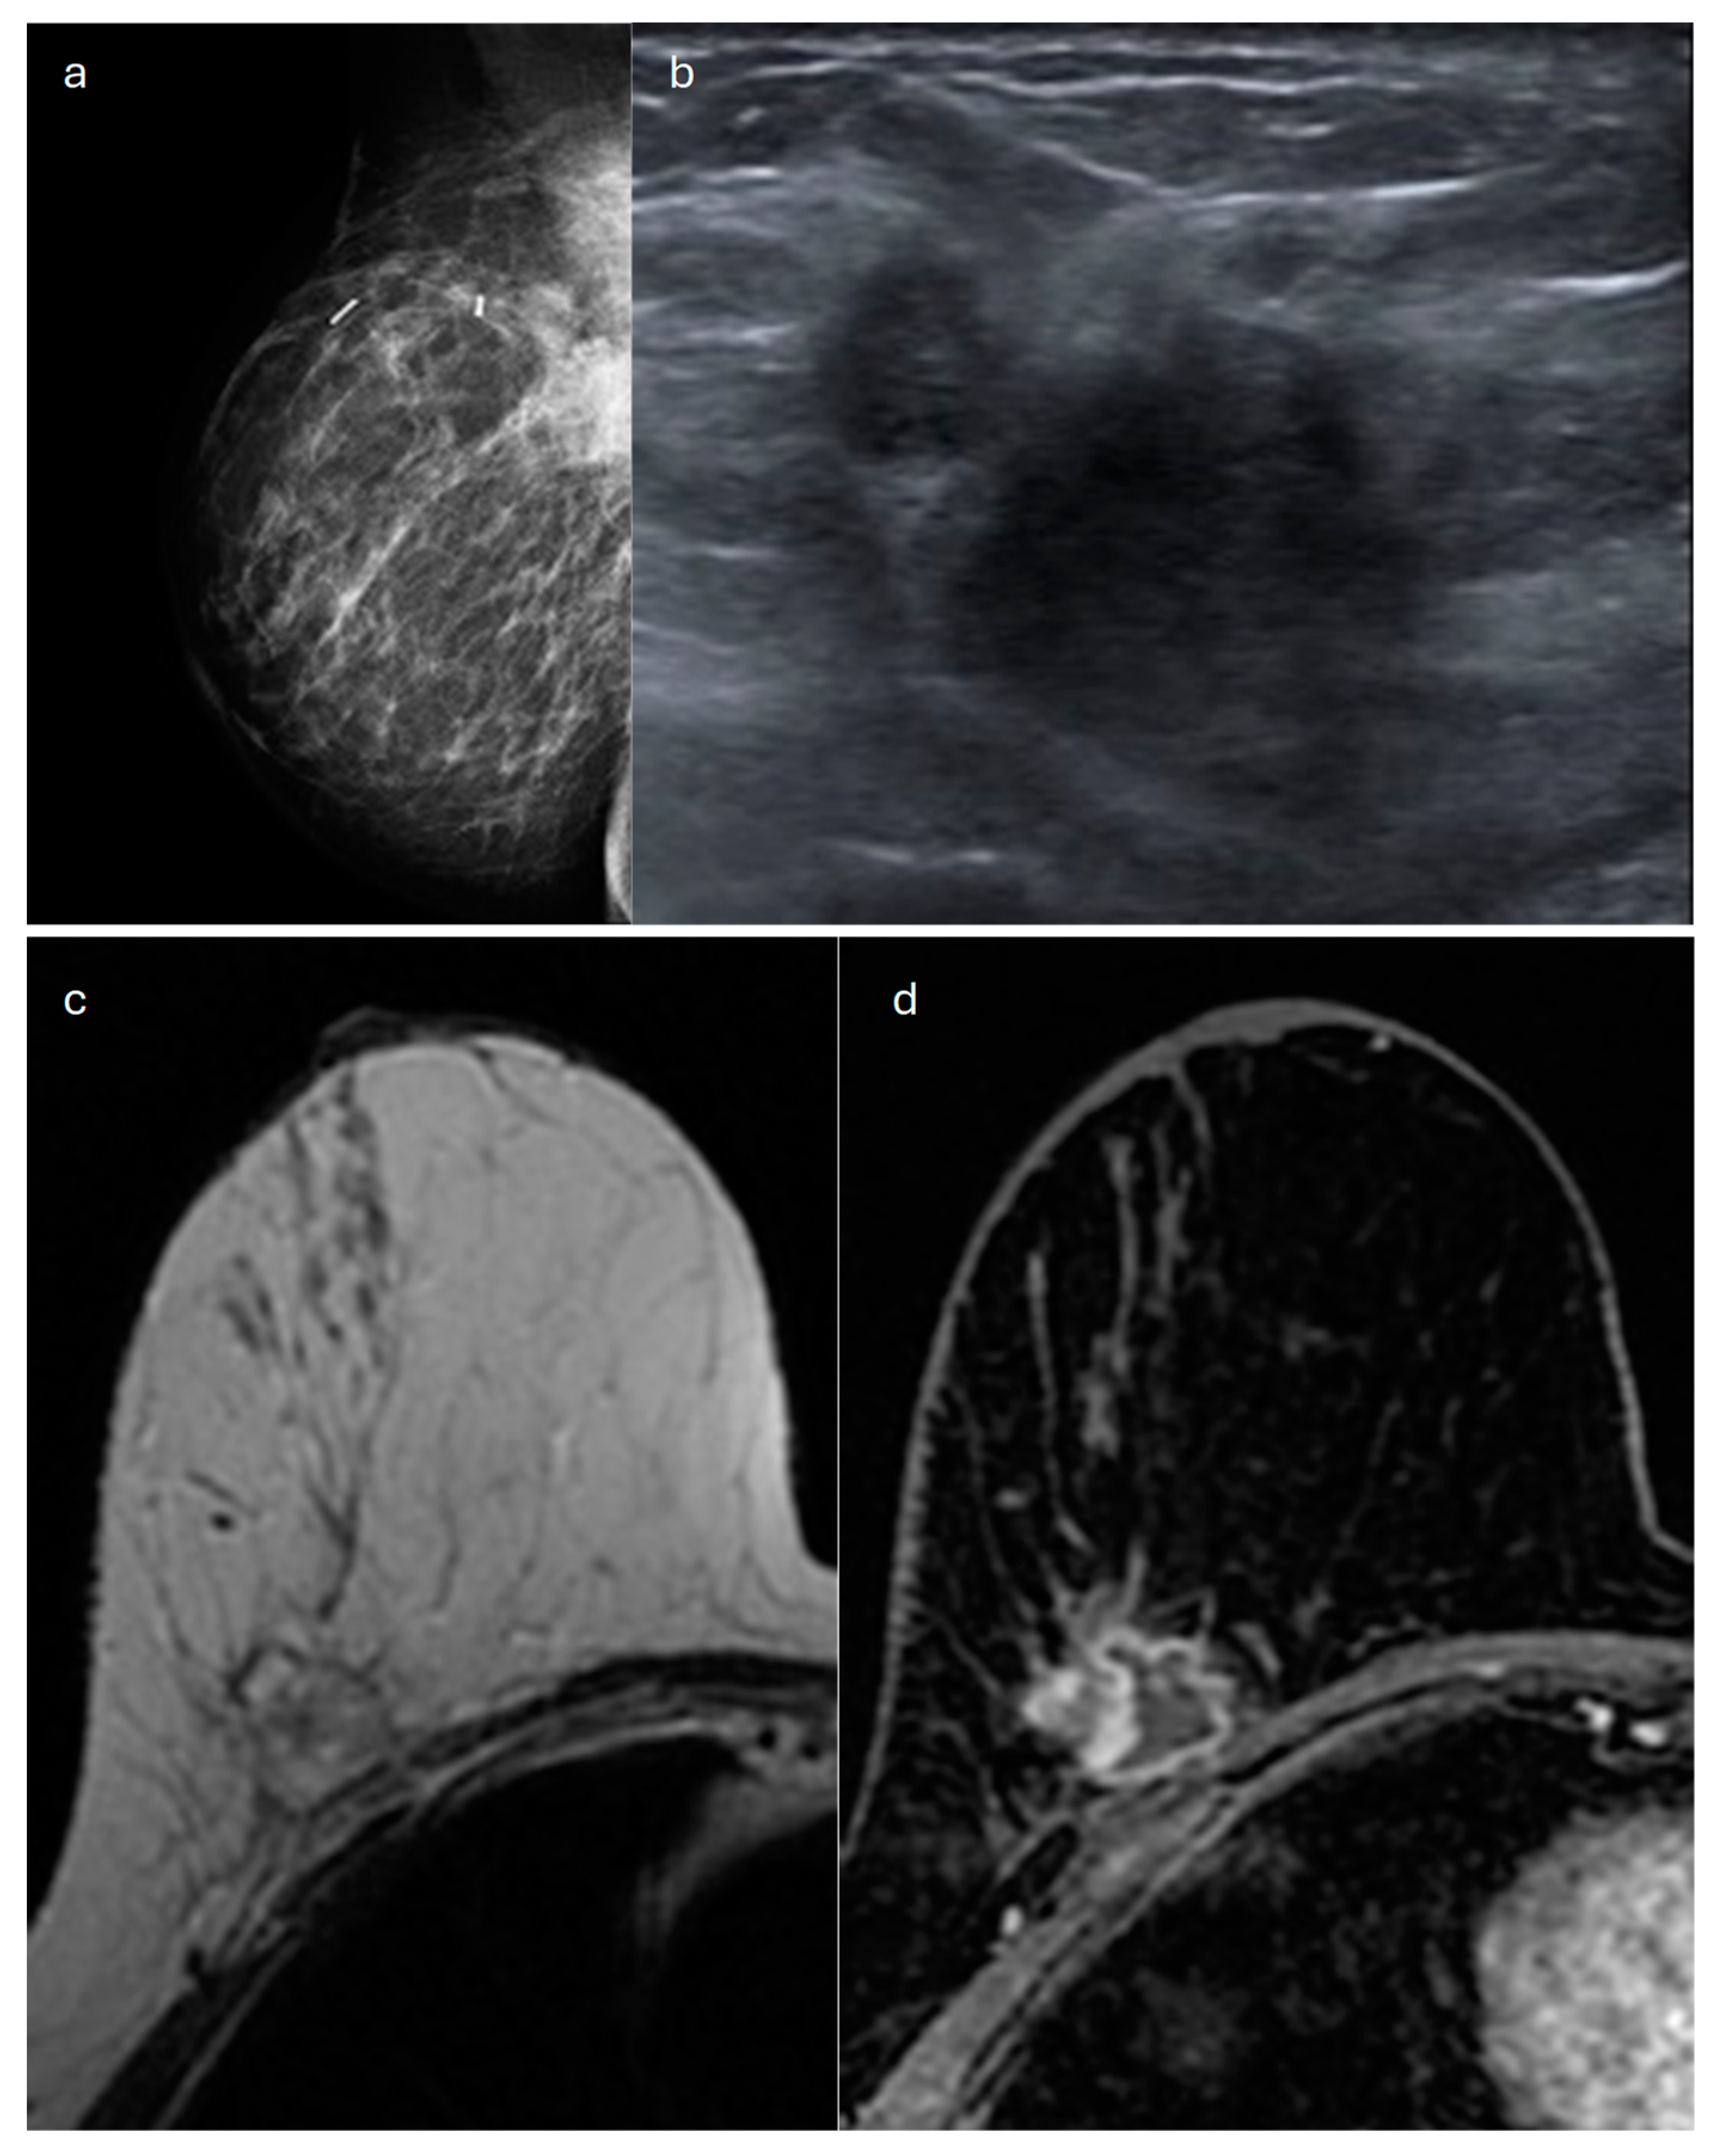

2. Lobular (Classic, Pleomorphic and Florid Types)